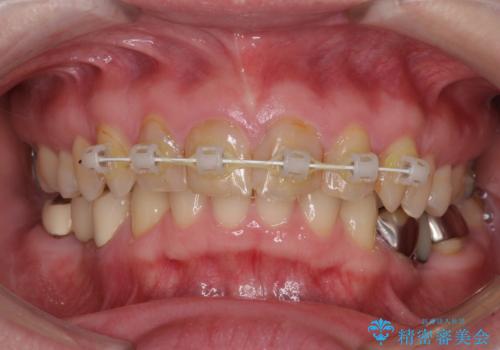

- 近医で奥歯が割れているので抜歯が必要と言われたとのことで来院された患者様です。

診断の結果、歯根が縦に破折しており抜歯が必要な状態でした。

抜歯してからインプラント埋入までには時間がかかるため、その間に下顎左右臼歯の金属のブリッジをオールセラミックへ変えていくこととしました。

継ぎ接ぎだらけの上顎前歯もオールセラミッククラウンにて審美的に改善したいとのことでしたが、捻れが強くあるため、事前に矯正治療で歯列を整えてから、補綴治療を行うこととしました。